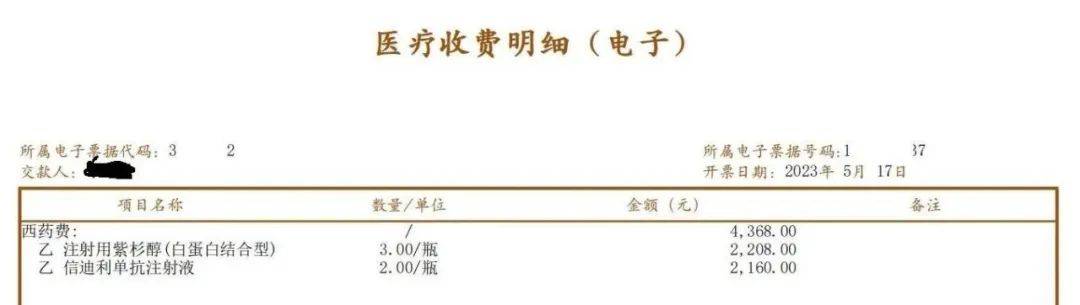

►关于白紫化疗药

紫杉醇(白蛋白结合型)以下简称“白紫”,在2022年国家集采名录里石药的一瓶135元,我爸也享用过。今年复用化疗,第一家医院只有江苏恒瑞的,一瓶736元。经了解,石药白紫一瓶228元,齐鲁的白紫一瓶100多。复用第二次就果断的换了医院,考虑石药做的最早,副反应也小,就用了石药的,一次三瓶省1524元。事后12345投诉第一家医院,医院给回复下次用药可以从第二家医院给我爸调石药的。

图片来源:患者提供